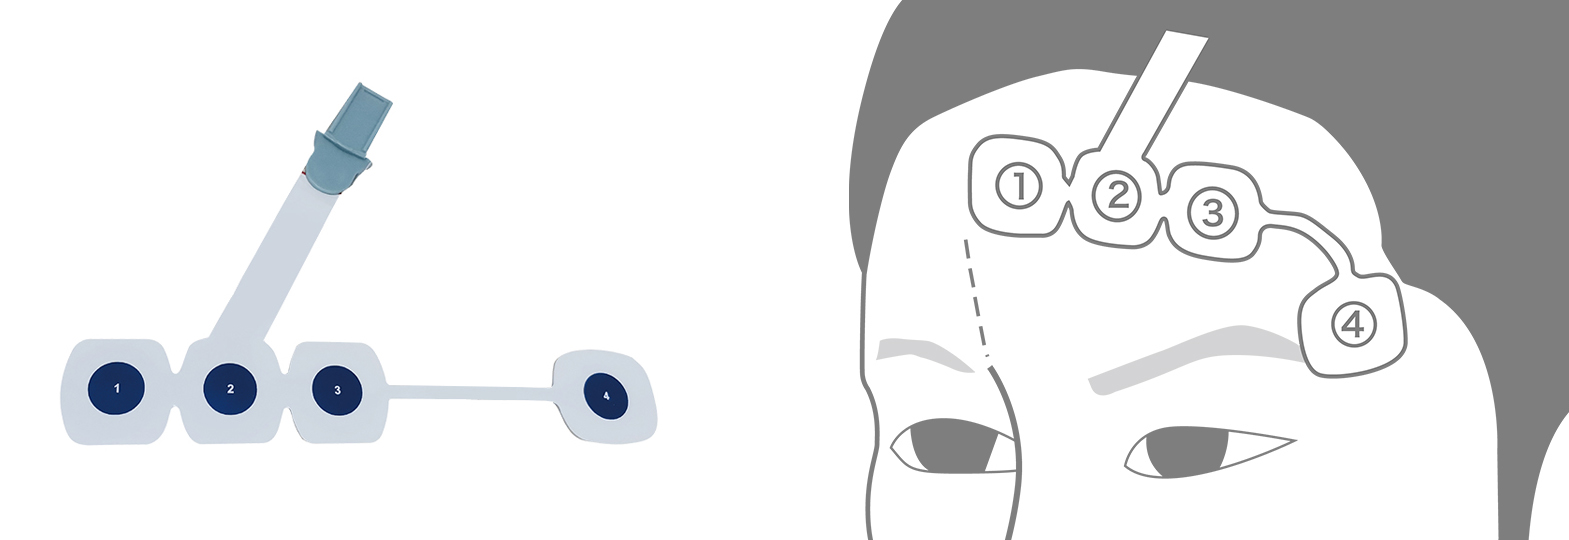

Integrated sensor design

Adopt disposable sensor design, using flexible PCB cable and electrode to adopt integrated design, add special intelligent certification technology, ensure that the EEG sensor matches the machine use, limit the use time to ensure the signal quality in the use process.And using the independently developed conductivity electrode.

with high performance conductive effect and very small contact impedance, to ensure the quality of the signal acquisition.